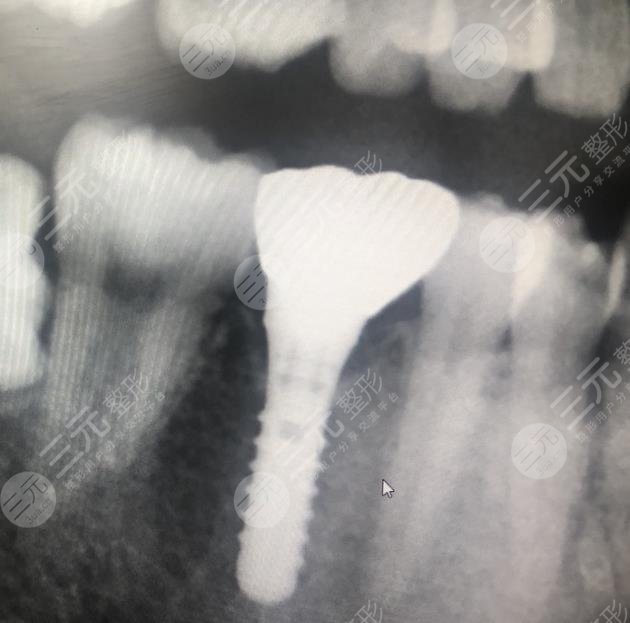

我到了昆明尚爱韩美口腔医院进行详细的检查之后,医生告诉我现在可以通过种植牙齿方式GET改良的果,但在种植牙齿的时候,我一直不知道会不会遇到副作用,所以我特别的紧张。在种植牙齿开始的时候,医生给我进行了消毒,整个种植牙齿的过程,经历了大概一个星期左右中间需要打磨以及开始种植,在开始种植的时候有一点点出血,但是并不是特别的大,医生告诉我修养大概一个星期左右的时间就能够恢复,不过在开始的时候吃东西一点都不舒服。